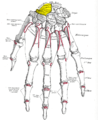

Scaphoid shown in yellow. Left hand. Palmar surface. Scaphoid shown in yellow. Left hand. Dorsal surface.

Scaphoid shown in yellow. Left hand. Dorsal surface. Cross section of wrist (thumb on left). Scaphoid (labelled as "Navicular") shown in red.